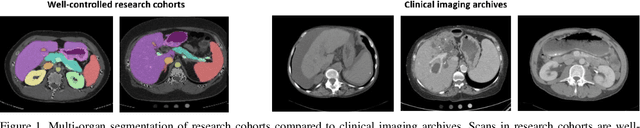

Abstract:Segmentation of abdominal computed tomography(CT) provides spatial context, morphological properties, and a framework for tissue-specific radiomics to guide quantitative Radiological assessment. A 2015 MICCAI challenge spurred substantial innovation in multi-organ abdominal CT segmentation with both traditional and deep learning methods. Recent innovations in deep methods have driven performance toward levels for which clinical translation is appealing. However, continued cross-validation on open datasets presents the risk of indirect knowledge contamination and could result in circular reasoning. Moreover, 'real world' segmentations can be challenging due to the wide variability of abdomen physiology within patients. Herein, we perform two data retrievals to capture clinically acquired deidentified abdominal CT cohorts with respect to a recently published variation on 3D U-Net (baseline algorithm). First, we retrieved 2004 deidentified studies on 476 patients with diagnosis codes involving spleen abnormalities (cohort A). Second, we retrieved 4313 deidentified studies on 1754 patients without diagnosis codes involving spleen abnormalities (cohort B). We perform prospective evaluation of the existing algorithm on both cohorts, yielding 13% and 8% failure rate, respectively. Then, we identified 51 subjects in cohort A with segmentation failures and manually corrected the liver and gallbladder labels. We re-trained the model adding the manual labels, resulting in performance improvement of 9% and 6% failure rate for the A and B cohorts, respectively. In summary, the performance of the baseline on the prospective cohorts was similar to that on previously published datasets. Moreover, adding data from the first cohort substantively improved performance when evaluated on the second withheld validation cohort.